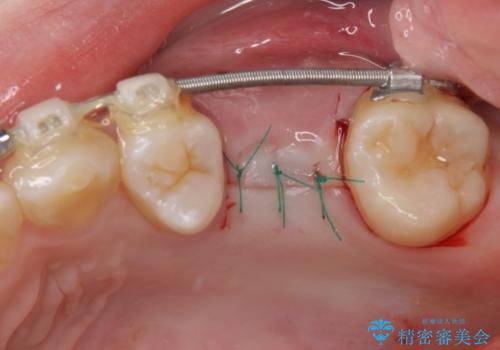

舌のトレーニングをしっかりと行っていただきながらワイヤー装置により矯正治療を行い、途中でインプラントを埋入し、矯正治療後に補綴治療を行うこととしました。